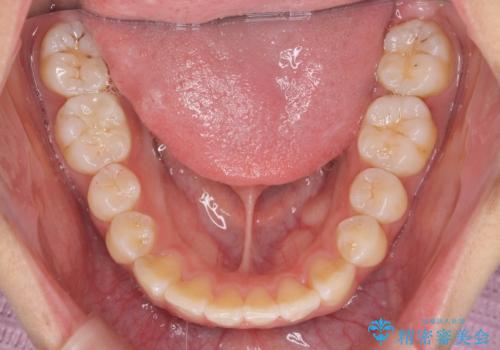

- 前歯の目立つねじれを矯正治療で治したい、と来院されました。

マウスピース矯正を始める前に、ねじれを取るのが短期間で済む部分ワイヤー小矯正を行うことで、全体的な治療期間を短くする治療計画を実行していきます。

前歯のねじれはマウスピース矯正の苦手な動きになり、治療期間が長くなる原因になりやすいです。